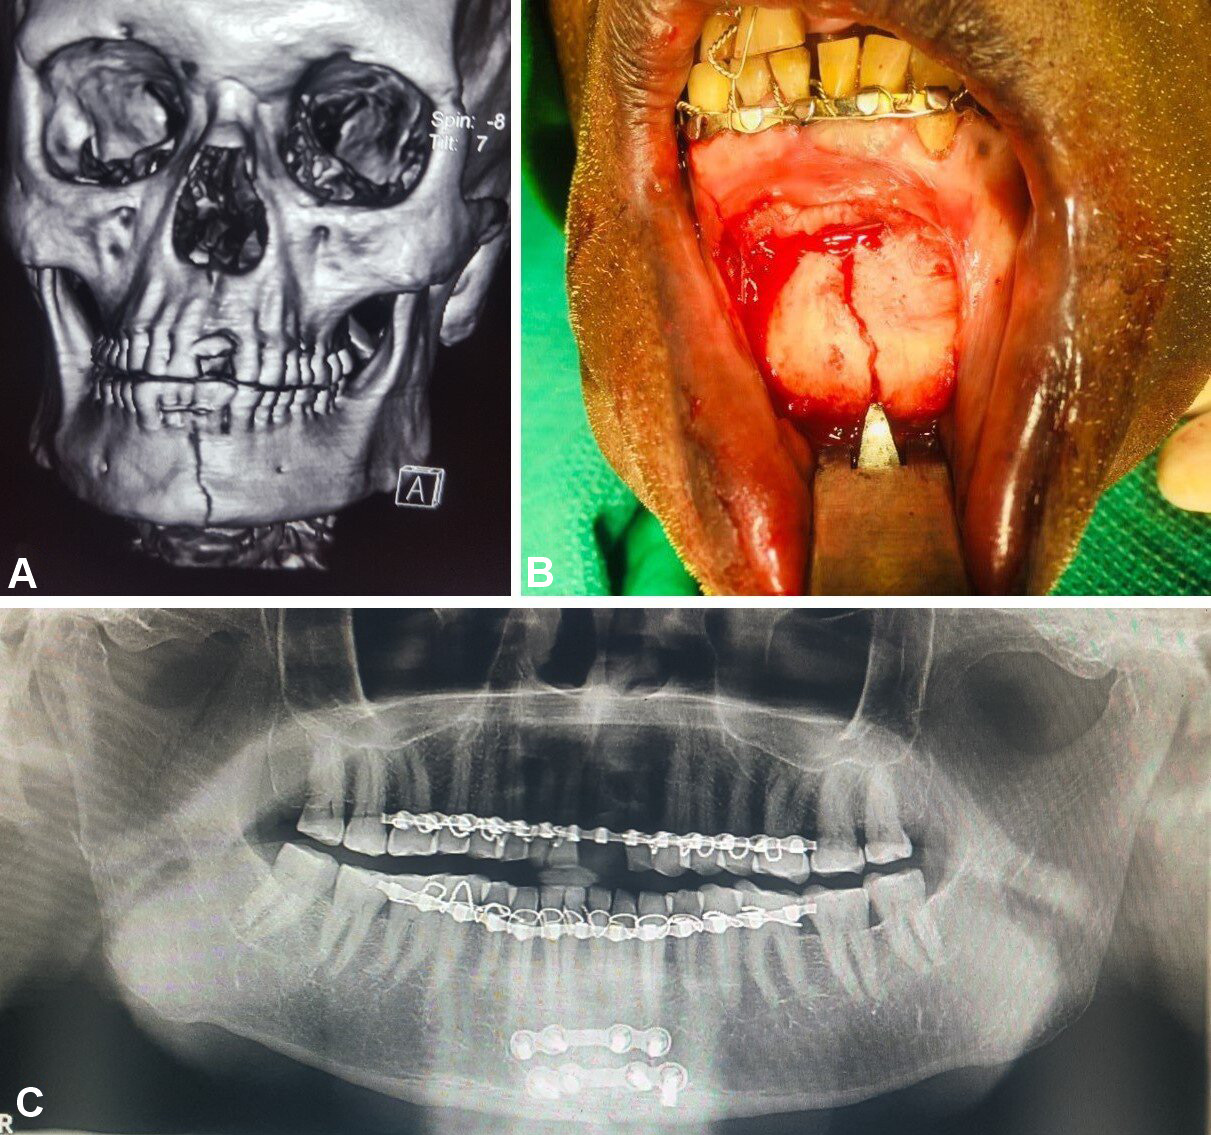

Patients with comminuted mandibular fractures, concomitant midface and dentoalveolar fractures, infected fractures, partial or complete edentulism, and systemic diseases were excluded from the study. Detailed preoperative medical and clinical examinations were conducted. The diagnosis of undisplaced or minimally displaced symphyseal or parasymphyseal fractures was based on clinical and radiographic assessments. Orthopantomograms were used to evaluate mandibular lower border displacement, with displacements of less than 5 mm included in the study (Figure 1). Advanced diagnostic techniques, including low-dose radiation and 3D assessments using computed tomography (CT), cone beam computed tomography and magnetic resonance imaging, facilitate comprehensive evaluation of head and neck disorders, including the assessment of both soft and hard tissue injuries.5, 6, 7 Therefore, CT with 3D reconstruction of the face was performed, with fractures exhibiting bucco-lingual overlap of less than 5 mm included in the study (Figure 1).

In group A, fixation was performed using 2 titanium microplates (0.8-mm, 4-hole design with a gap) and 8 microscrews (1.5 mm × 8 mm and 1.5 mm × 10 mm), which were placed subapically and at the inferior border of the mandible according to Champy’s lines of osteosynthesis (Figure 2, Figure 3, Figure 4).

In group B, fixation was conducted using 2 titanium miniplates (2.0-mm, 4-hole design with a gap) and 8 miniscrews (2 mm × 8 mm and 2 mm × 10 mm), which were positioned subapically and at the inferior border of the mandible according to Champy’s lines of osteosynthesis (Figure 5, Figure 6, Figure 7).